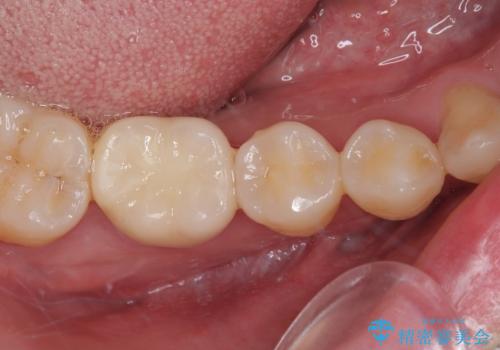

上顎は仮歯に置き換えた後に、それまでの痛みは一切感じなくなり、下顎も一度目の根管治療で痛みを感じることはなくなりました。

根管治療を行った歯の周辺にある病変は数ヶ月後にレントゲン写真を撮って確認する必要があるため、今後経過観察を行っていく予定です。